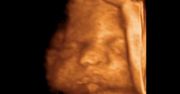

W piątek wyszła na jaw bulwersująca historia jednej z matek ze Świebodzina. Do tamtejszego szpitala około szóstej rano trafiła rodząca kobieta. Pomimo pośpiechu jej i męża, poród nie miał końca, a co gorsze, kobieta zaczęła słabnąć. Wtedy zaczęli z mężem prosić o wykonanie cesarskiego cięcia, które pozwoliłoby jej urodzić. Małżeństwo trzy razy próbowało nakłonić lekarza do zmiany decyzji i pomocy, a kolejne godziny mijały. W końcu doszło do drastycznego porodu - dopiero o godzinie 20:00, czyli 14 godzin odkąd matka trafiła do szpitala. Niestety, dla dziecka było już za późno. Nie przeżyło. W odpowiedzi na tę i inne historie minister zdrowia Konstanty Radziwiłł w TVN24 stwierdził, że lepszym rozwiązaniem zarówno dla matki, jak i dziecka jest poród naturalny. Podkreślił zarazem, że kobieta w trakcie porodu ma prawo do znieczulenia, nie może natomiast żądać cesarskiego cięcia. Lepszym rozwiązaniem jest poród naturalny, zarówno dla mamy, jak i dziecka. Nie ma mowy, żeby wprowadzić program cesarskiego cięcia na żądanie. Tam gdzie kobieta oczekuje znieczulenia, powinno być jej zapewnione, ale to nie dotyczy cięcia cesarskiego. Zdaniem ministra lepiej skazywać matkę na 14 godzin porodu i urodzenie martwego dziecka, niż odpowiedzieć na jej prośby? W tym wypadku żądanie wydaje się być mocno niewłaściwym słowem.

Siostra kobiety rodzącej na podłodze: Było 8 osób na dyżurze, nikt nie pomógł